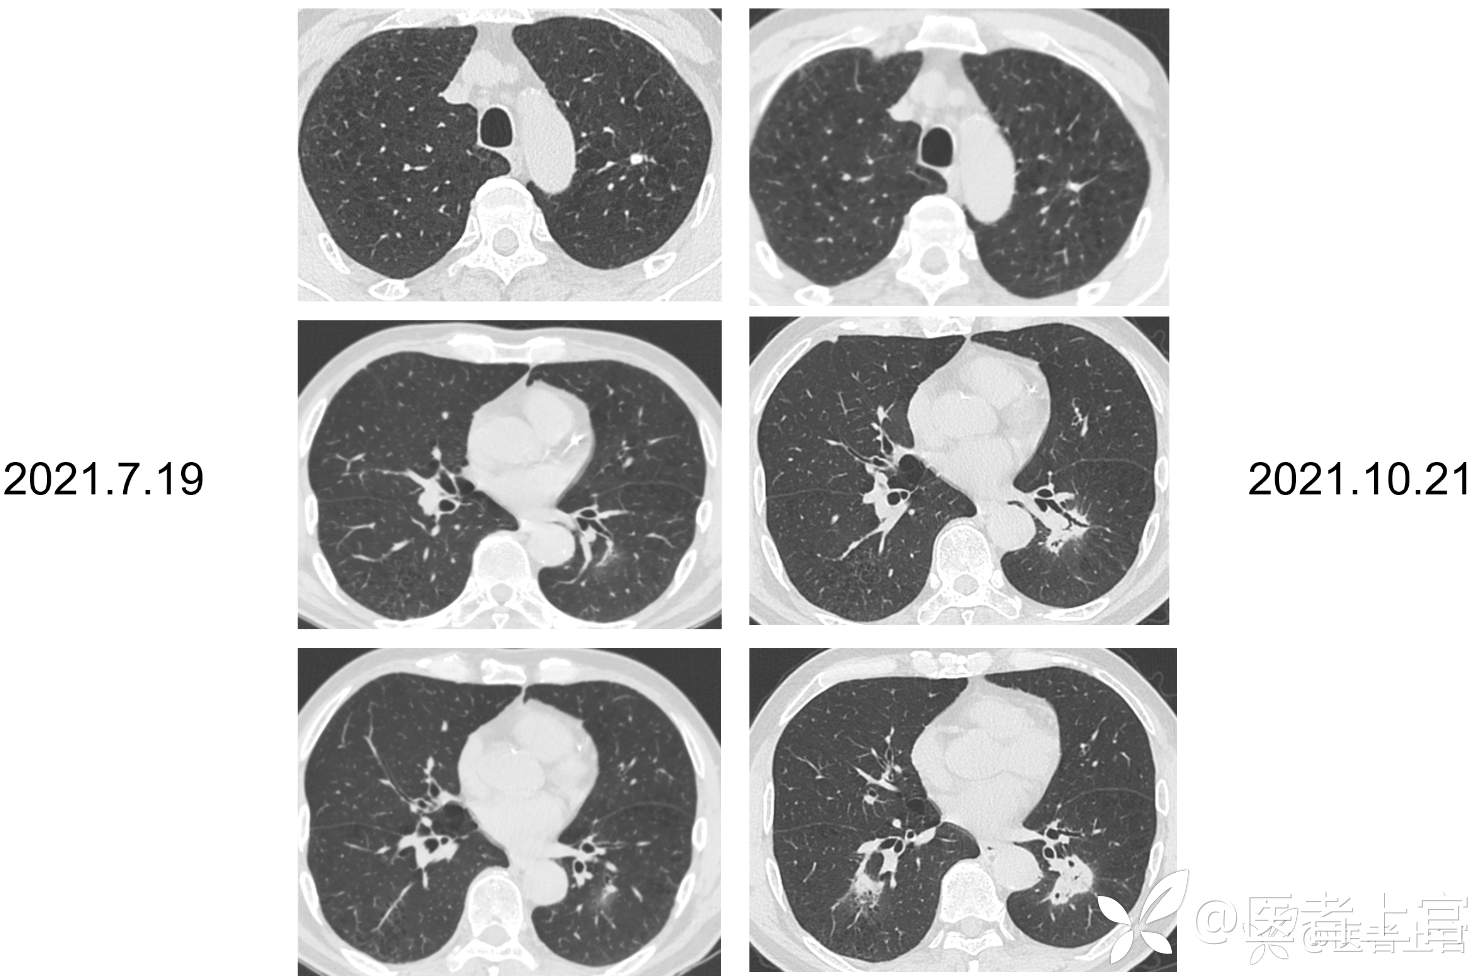

【7.19肺CT】两下肺斑片模糊影,渗出可能,建议抗炎后复查。两肺局限性肺气肿;左肺上叶及右肺下叶背段纤维、结节状钙化灶伴右肺下叶局部支气管牵拉扩张

【10.21肺CT】两下肺模糊实变灶,较前片(2021-7-19)进展,首先考虑炎症,建议抗炎治疗后短期复查。两肺局限性肺气肿;左肺上叶及右肺下叶背段纤维、结节状钙化灶伴右肺下叶局部支气管牵拉扩张。主动脉、冠脉硬化。

【7.19肺CT】两下肺斑片模糊影,渗出可能,建议抗炎后复查。两肺局限性肺气肿;左肺上叶及右肺下叶背段纤维、结节状钙化灶伴右肺下叶局部支气管牵拉扩张。主动脉、冠脉硬